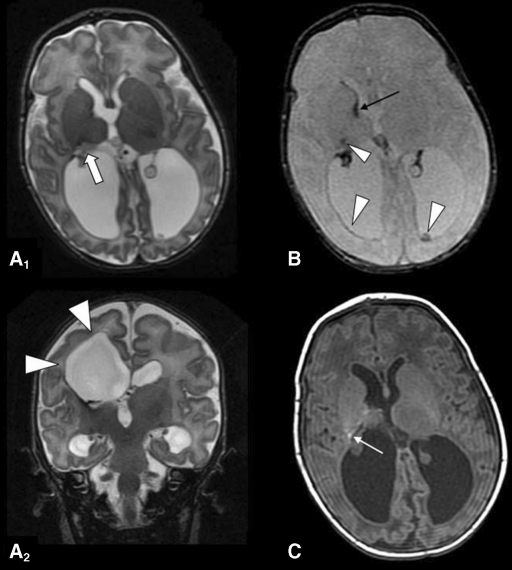

We describe pre-and post-surgical clinical features along with neuroradiological results by magnetic resonance imaging(MRI),functional magnetic resonance imaging(fMRI),MR-tractography(MRT),and neurophysiological study by single and paired pulses transcranial magnetic stimulation(TMS)in a child with cerebral palsy with epileptic encephalopathy,eligible for epilepsy surgery.

Presurgical TMS evaluation showed a lateralization of motor function on the left motor cortex for both arms,and results were confirmed by MRI studies.Interestingly,after surgery,both epilepsy and motor performances improved and TMS showed enhancement of intracortical inhibition and facilitation activity.

我們通過磁共振成像(MRI),功能磁共振成像(fMRI),MR描記術(shù)(MRT)以及單脈沖和成對脈沖經(jīng)顱磁刺激的神經(jīng)生理學研究,描述術(shù)前和術(shù)后的臨床特征以及神經(jīng)放射學結(jié)果(TMS)在患有癲癇性腦病的腦癱患兒中,適合進行癲癇手術(shù)。

術(shù)前經(jīng)顱磁共振成像(TMS)評估顯示雙側(cè)手臂左側(cè)運動皮質(zhì)的運動功能偏側(cè)化,結(jié)果經(jīng)MRI研究證實。然而,術(shù)后癲癇和運動能力都得到好轉(zhuǎn),TMS顯示皮質(zhì)內(nèi)控制和促進活動增強。